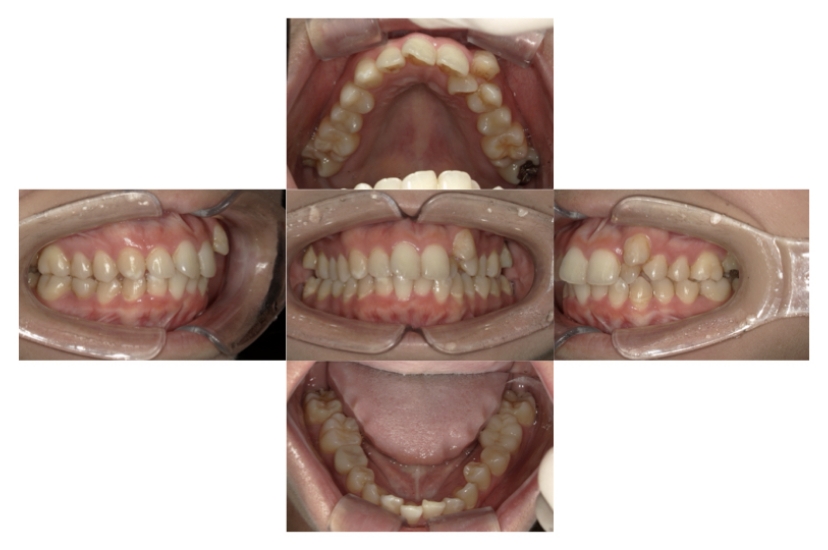

BEFORE

AFTER

上下顎叢生(上下の前歯のガタガタ)のケースです。

装置はラビアル(上下表側)で、上下顎の小臼歯を4本抜歯を行っています。抜歯したスペースを使って、上下の前歯の後方移動と叢生(ガタガタ)の改善を行っています。

主訴 八重歯を治したい。

年齢・性別 25歳 女性

お住まいの地域 神奈川県川崎市

治療方針 抜歯スペースを利用して上前歯の叢生(ガタガタ)の改善

抜歯部位 上下顎左右第一小臼歯

使用装置 ラビアル(上下表側)、顎間ゴム

治療期間 1年11か月

治療回数 16回

リテーナー クリアリテーナー